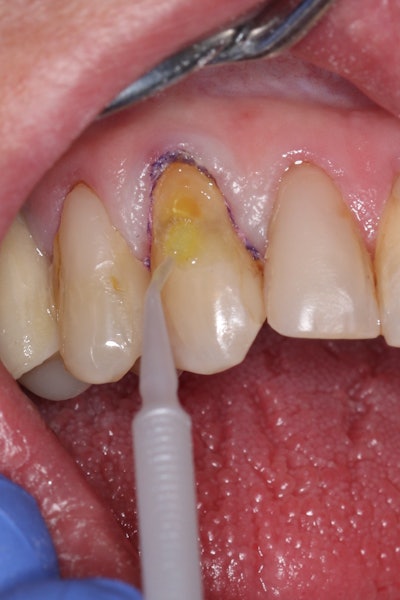

The tooth was evaluated using a caries indicator dye (Kuraray Noritake Dental), helping to identify any remaining infected tissue beneath the dislodged composite (Figure 3).

Figure 3: Application of caries indicator dye to identify remaining infected tissue beneath the dislodged composite.Figure 3: Application of caries indicator dye to identify remaining infected tissue beneath the dislodged composite.